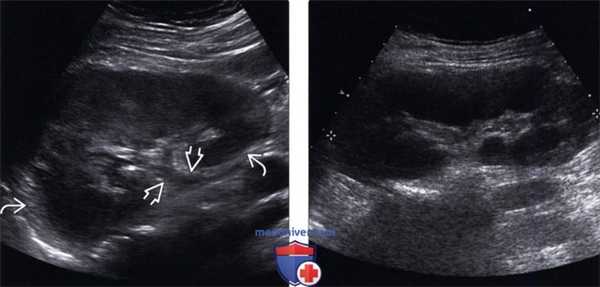

(Левый) На продольном УЗ срезе визуализируется практически полное отсутствие кортико-медуллярной дифференциации в инфицированной отечной почке. Визуализируется утолщение уротелия почечной лоханки и проксимального отдела мочеточника. Повышенная эхогенность воспаленной околопочечной клетчатки.

(Правый) На продольном ультразвуковом срезе визуализируется диффузная гипоэхогенная и отечная почка вследствие пиелонефрита.

(Левый) На продольном УЗ срезе у пациента с острым пиелонефритом визуализируется увеличенная гипоэхогенная почка со снижением кортико-медуллярной дифференциации. Почечная пазуха уплощена вследствие диффузного отека почки.

(Правый) На продольном УЗ срезе с цветовой допплерографией визуализируется слабый периферический кровоток у того же пациента с острым пиелонефритом и отечной почкой.